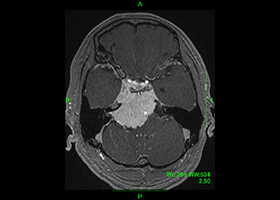

症例3)31歳男性、延髄前面巨大舌下神経鞘腫

[画像所見]

-

嚥下困難、四肢麻痺で発症しました。 -

術前 -

術後 -

術後、患者さんは元気に自宅退院されました。